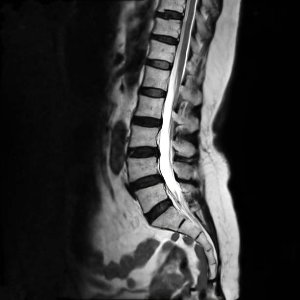

등허리 통증에 대한 일반적인 신념은 통증이 없다면 등허리는 건강하다는 것입니다. 그러나 1994년 Dr. Maureen Jensen의 연구는 새로운 시각을 보여줍니다. Dr. Jensen은 등허리 통증 경험이 없는 98명의 개개인에게 MRI 검사를 실시했습니다. 놀랍게도, 그중 63명의 사람들이 디스크 병변이 발견되었습니다. 더욱 놀라운 것은 이 중 일부 개인은 MRI 검사 당시 등허리 통증이 없었으며 척추에 관련된 이전 의학적 문제도 없었다는 것입니다(MRI에서 디스크는 발견되었지만 통증이 없는 사람들).

이 결과는 다양한 디스크 문제를 보여주었습니다. 디스크 돌출 (52%), 디스크 탈출 (28%), 종판 손상 (19%), 섬유륜 손상 (14%) 및 후관절 변성 (8%) 등이 있었습니다. 이러한 결과는 일상생활에서 특정 등 부상이 없어도 요추 디스크 손상이 흔히 발생할 수 있음을 보여줍니다. 본질적으로, 이는 등허리에서 통증이 있지 않더라도 디스크의 손상과 병변이 있을 수 있음을 말해줍니다.

Stanford University School of Medicine의 정형외과 교수 인 Dr. Eugene Carraghy는 등허리 통증과 무증상 디스크 병변 사이의 관계를 더 깊게 연구했습니다. 그녀는 등허리 통증을 경험한 적이 없는 200명의 개인을 모집하고 MRI를 실시했습니다. 5년 동안 그들의 건강을 모니터링하고 일부 참가자들의 심한 등허리 통증이 발생한 후에 촬영된 MRI를 이전 MRI와 비교했습니다. 놀랍게도, 통증이 극심한 경우에도 비교된 MRI 이미지에서 새로운 병변이 있는 것은 두 명뿐이었습니다.